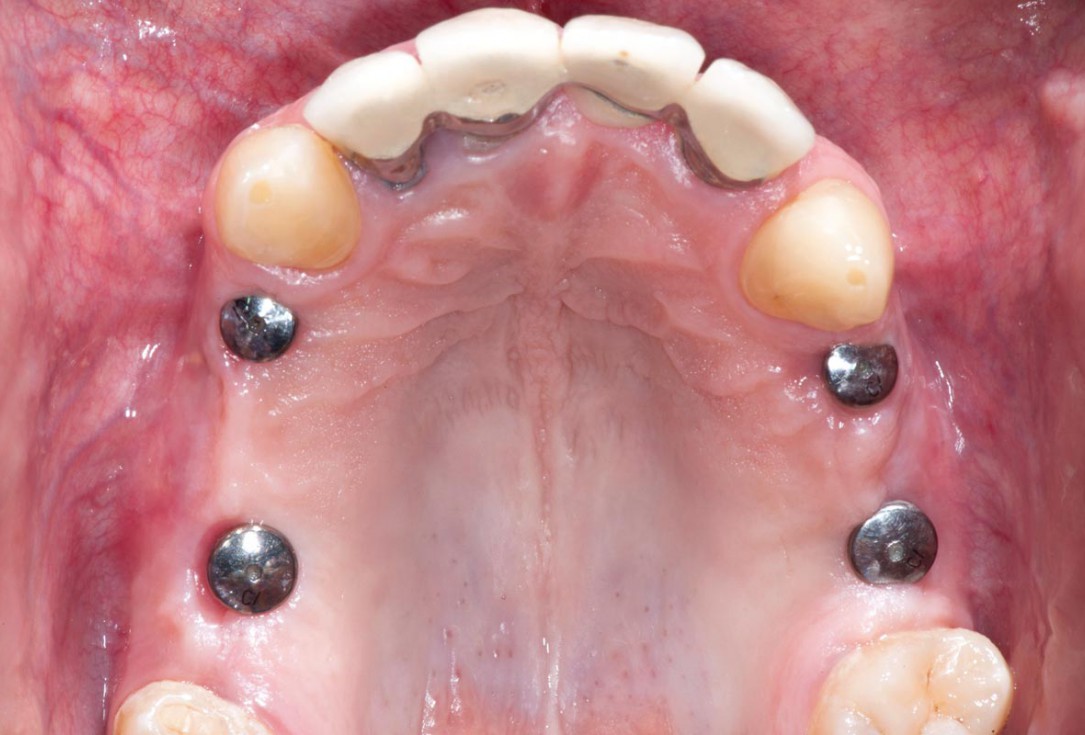

Periimplantitis treatment with maxgraft® bonering - Dr. B. Giesenhagen

Severe periimplantitis at tooth 15 with bone loss up to 1/3 of the implant